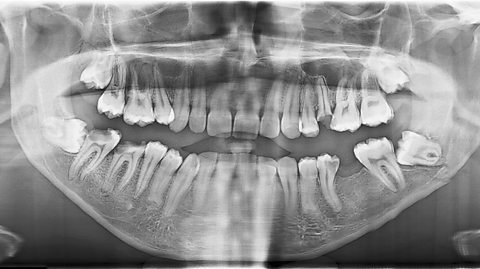

Humans have two different sets of teeth in our lifetime, our milk teeth, sometimes known as baby teeth, and our adult teeth. Generally, children will have 20 milk teeth, 10 on the top row and 10 on the bottom, which tend to come in between the ages of six and 12 months.

Milk teeth then tend to fall out around the ages of five or six, with adult teeth coming in shortly thereafter. Adults have more teeth than children, totting up to 32 teeth, with an equal amount across the top and bottom.

For the most part, people will have a full set of adult teeth by their teenage years, made up of eight incisors, four canines, eight premolars, and 12 molars. To find out more about the different types of teeth, check out this guide from BBC Bitesize.

Wisdom teeth are the third set of molars which sit at the back of the mouth, generally being the final of our 32 adult teeth to come through.